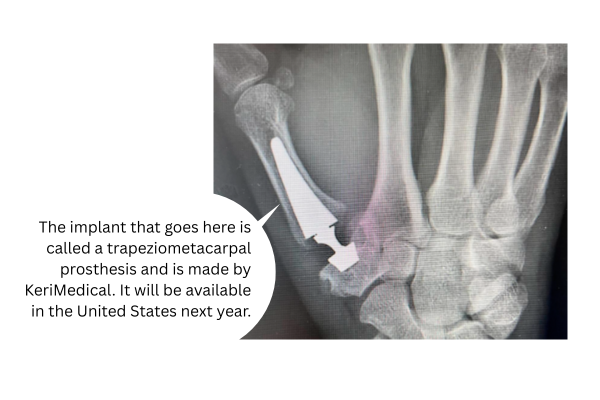

KeriMedical develops and manufactures implants for hand and wrist surgery.

The FDA gave final approval to the KeriMedical TOUCH prosthesis — a thumb implant — on July 10.

The device, already available outside of the United States, is used to treat osteoarthritis of the thumb’s basal joint. The implant provides patients with pain relief while also restoring strength and mobility.

In preparation for the US market launch of the TOUCH thumb prosthesis in early 2026, Medartis has established a comprehensive surgeon training program, designated reference centres, and selected key opinion leaders, the new release said.